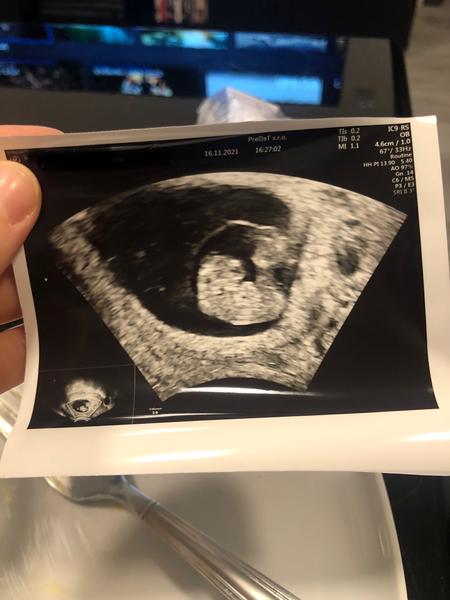

Dnes 8+0 dle posledního ultrazvuku...

@misaa56 Dobré ranko, tak dnes takto🥰